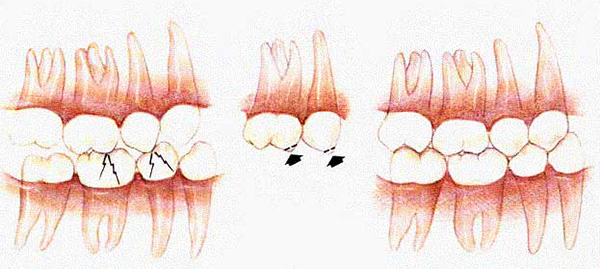

La foto sotto mostra ciò che provoca l'abrasione dei denti a causa di un'occlusione impropria nella regione anteriore:

Normalmente, i denti laterali delle mascelle superiore e inferiore non devono rimanere sullo stesso piano quando sono chiusi. Cioè, i molari devono avere una certa inclinazione, in modo che con vari movimenti della mascella inferiore, i denti laterali non perdano il contatto tra loro. In presenza della corretta inclinazione dei denti, si formano linee tracciate condizionatamente - curve occlusali:

Data la forma delle curve occlusali, un ortodontista può rivelare segni di un morso permanente irregolare quando un paziente viene esaminato attentamente.